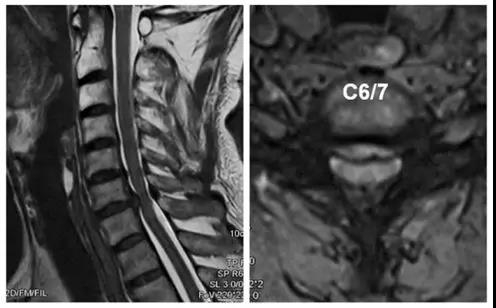

诊断:颈椎病(C6/7)

术前X线正、侧位片

术前CT

术前核磁

术后X线正、侧位片